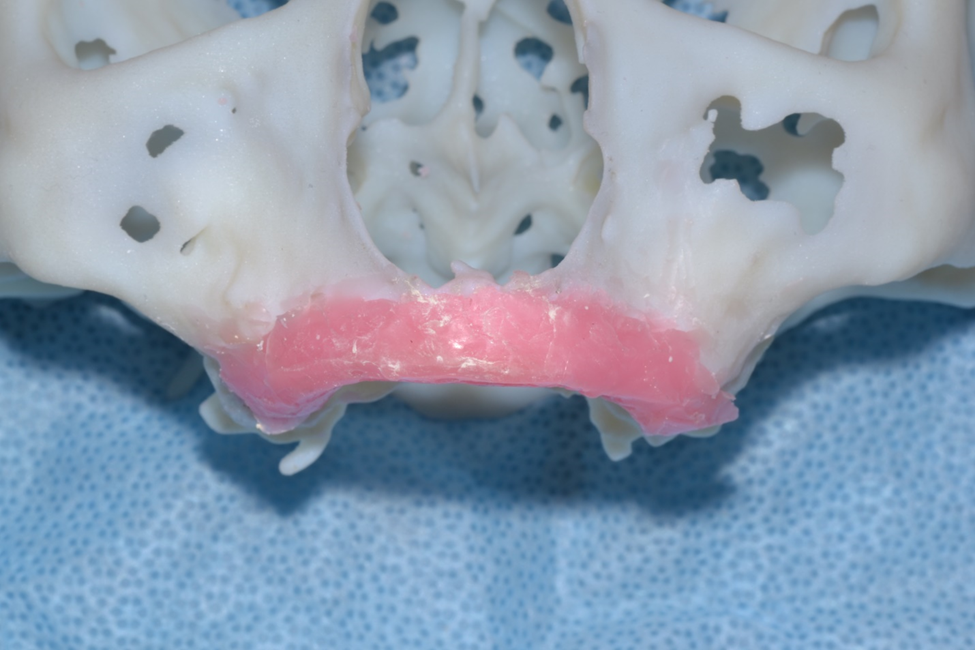

The titanium crib was custom fabricated prior to surgery. Early on this was accomplished by taking impression of the arch. The study model was waxed-up to desired ridge dimensions and then an acrylic model was made of the wax up. The titanium crib was bent to desired shape on the model. With the development of cone beam CT scan, inexpensive 3-D printed models were produced which allow direct wax up on the representative bone anatomy (Case 1: Figures 1-5). More recent technology introduced by Geistlich Pharma called Yxoss CBR, utilizes a software program for virtual augmentation to create a titanium crib based on the surgeons preference. It also computes the volume needed in graft material. The authors have only recently started to use this technique, but it does not include any patients in this study.

Figure 2a. 3-D model reconstructed from preoperative conebeam ct scan revealing severe atrophy down to the nasal floor.

Figure 2b. Wax up of desired ridge height and width. An impression is made and poured up in acrylic for bending of titanium crib for graft containment.

Figure 3 (a & b). Acrylic model with creation of titanium crib contoured and trimmed.